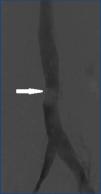

Se realizó ecografía abdominal objetivándose masa retroperitoneal de unos 8 cm, de ecogenicidad heterogénea y marcada vascularización. Ante este hallazgo se realizó tomografía axial computarizada (TAC) abdómino-pélvica, donde se confirmó la existencia de una masa retroperitoneal de 8 x 4 cm por encima de la bifurcación aórtica, que infiltraba la vena cava inferior y bordeaba la aorta en 180º englobando a la arteria mesentérica inferior (figura 1). Dados los hallazgos del TAC, se realizó cavografía para valorar la resecabilidad, observando un defecto de repleción intracava infrarrenal de 2 cm de diámetro (figura 2).

Figura 2. Cavografía